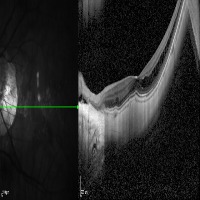

Medical Imaging Analysis: The "three-segment" model can be used by healthcare professionals for enhanced analysis of medical imaging, such as MRI or CT scans. It will help in identifying cleave classes, which can improve detection and diagnosis of potential issues in the brain, particularly those related to retina or neural connections.

Retinal Disease Diagnosis: Ophthalmologists could utilize the model to get help in diagnosing retinal diseases. It can help to identify any abnormalities by differentiating between the 'out', 'in', and 'retina' segments, enabling early detection of conditions such as retinal detachments or macular degeneration.

AI in Surgery: The model can be used to assist surgeons during complex neuro or eye surgeries. It can provide enhanced visualization, enabling real-time differentiation between various segments, leading to more precision in surgical procedures.

Medical Training and Education: The model can be used in medical learning settings, providing students with valuable visual learning material. It could serve as an advanced tool for the understanding of the retina and other segments of the brain or eye.